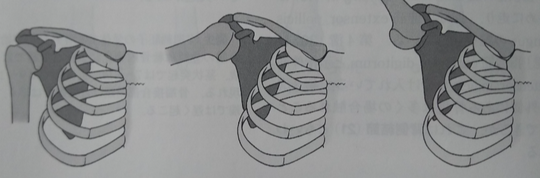

正常な肩関節の静止位置(左)、外転(中)、挙上(右)

健常な肩関節静止位置から外転、挙上による関節可動域の終着点は、上腕骨外科頸と肩峰の接触した時である。

患側の胸鎖関節が機能しない場合、肩関節外転は肩甲上腕関節が120度までの外転で限界となる。

肩甲上腕関節が機能しない場合、肩甲胸郭関節を十分に機能しても外転60度が限界である。

肩関節外転の際に、上腕の外旋が出来ない場合は全体の機能として可能な関節可動域は120度までであり、そのうちの60度は肩甲上腕関節60度、肩甲胸郭関節60度である。

上腕よりも肩甲骨が機能する場合が上図である。この状態がフローズン・ショルダー(凍結肩・五十肩)である。肩関節の外転に関して複数の筋の機能が調和して機能していないことが原因で、単独の筋の損傷だけでは説明がつかない。